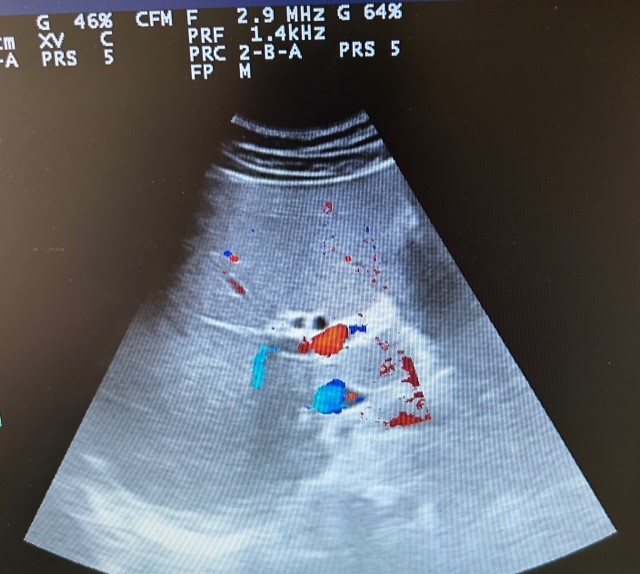

En la ecografía se observa ectasia de la vía biliar intrahepática conformando un patrón de doble carril.

Por los hallazgos ecográficos y de la exploración física se decide derivar a urgencias del hospital de referencia ante la sospecha de colecistitis aguda vs coledocolitiasis. En urgencias se realiza ecografía con resultado concordante con la realizada desde Atención Primaria.